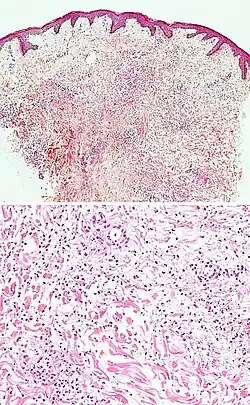

| Kaposi’s sarcoma in patch stage | The patch stage typically shows irregular proliferation of jagged vascular channels in the dermis below an integral epidermis. The so-called promontory sign is sometimes found in patch stage lesions and denotes vascular spaces surrounding pre-existing blood (see image).[23]

vessels |

|